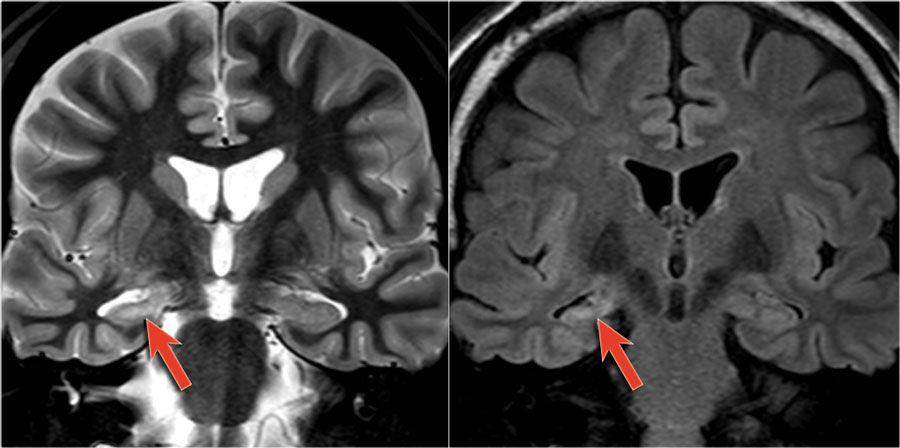

Figura 2: Edema Citotóxico en Hemiconvulsión-Hemiplejía

Cuando la RM cuenta la historia. 🧩 Esta imagen muestra borramiento surcal en el hemisferio izquierdo con hiperintensidad difusa en FLAIR y DWI, pérdida de señal en ADC y edema citotóxico. A pesar del compromiso hemisférico, el patrón respeta los núcleos profundos y excluye áreas vasculares específicas. Todo apunta a la fase aguda del síndrome hemiconvulsión-hemiplejía, demostrando la importancia de un análisis detallado.

Fuente: Pfleger R. Acute phase of hemiconvulsion-hemiplegia epilepsy syndrome. Case study. Radiopaedia.org. Consultado el 28 de enero de 2025. https://doi.org/10.53347/rID-29309.